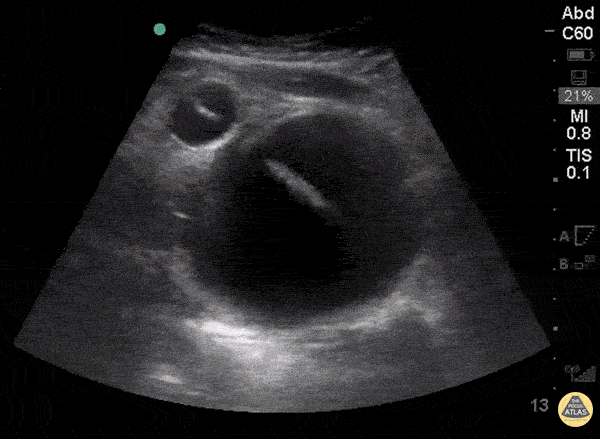

WCUME 2017 Submission for "Novel Indication" A urinary catheter is not draining appropriately and bedside ultrasound reveals inflated balloon caught within a bladder diverticulum. Under dynamic ultrasound guidance, the balloon is deflated, the catheter withdrawn into the bladder lumen, and then reinflated in the appropriate position. Sam Langberg, MD - Ochsner Medical Center, New Orleans, LA